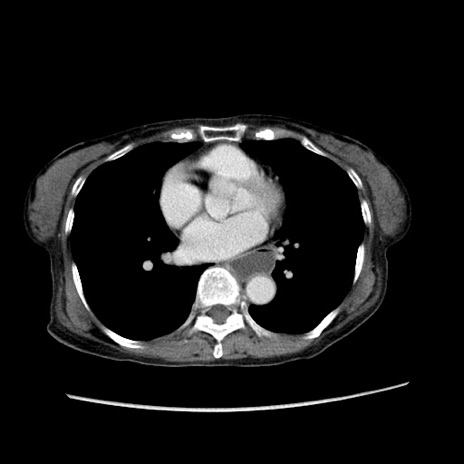

症例25(横断像)

【症例】80歳代女性

【主訴】胸のつかえ感

【現病歴】約9時間前に食後から胸のつかえた感じあり、嘔吐あり、来院。

【既往歴】胃癌(全摘)、胆摘、虫垂炎

【身体所見】心窩部に圧痛あり、反跳痛なし。

【データ】WBC 5700、CRP 0.05